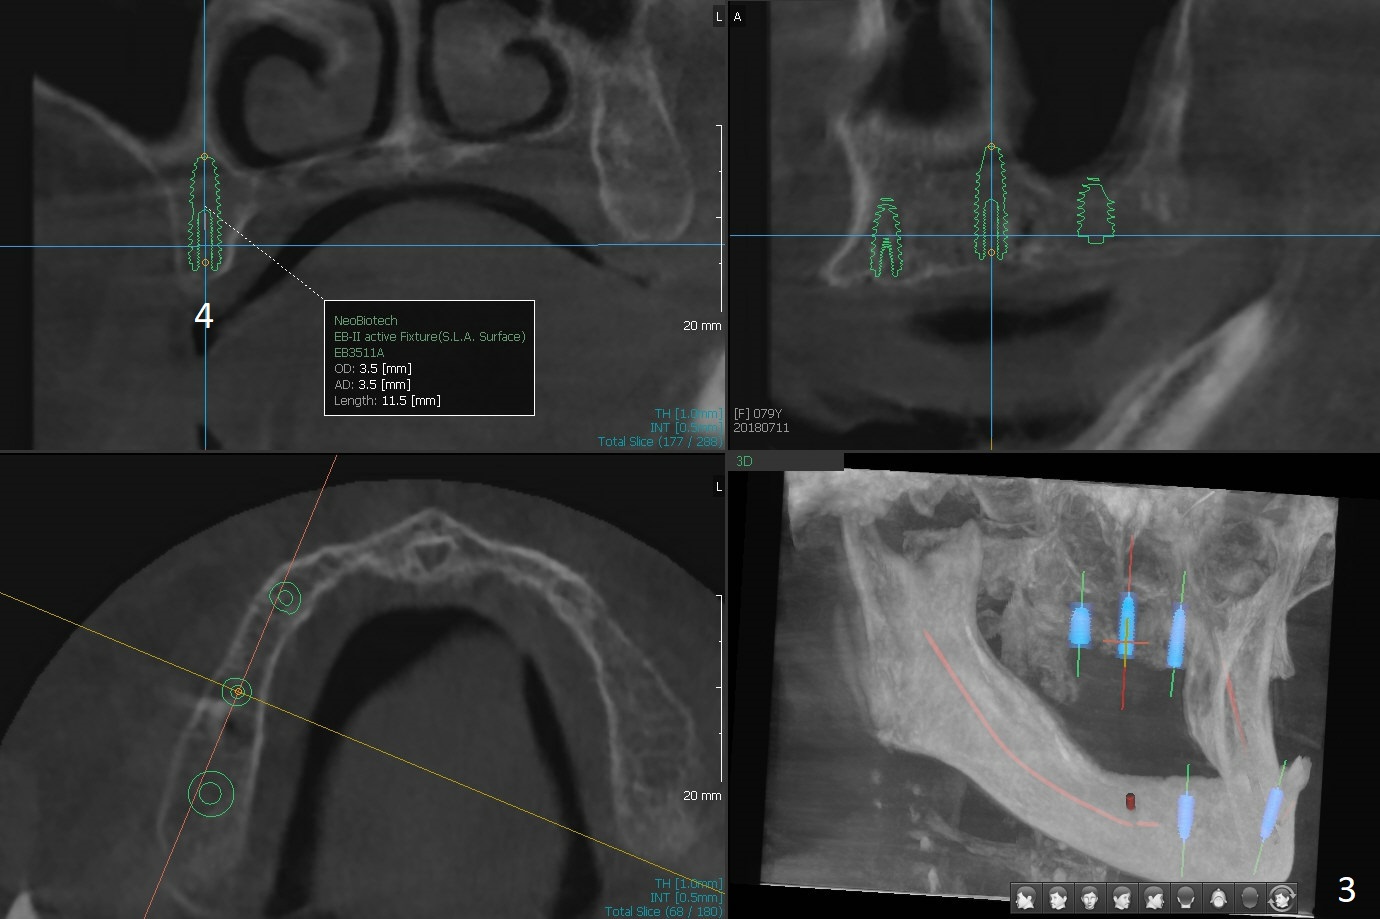

A 80-year-old woman wants to correct cross bite of complete dentures (Class II relationship). It seems that implant supported overdentures can make it possible (retention). Six implants will be placed in the maxillary canine and 2nd premolar and 2nd molar areas with surgical guide (Fig.1-6 (anterior ridge narrow)). Bone density is low. Prepare soft reline.